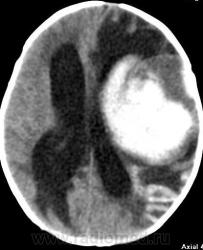

Я думаю, это больше похоже на кровоизлияние - неоднородная структура с гиперденсным компонентом. Плюс ко всему - клиника, судя по всему, с острым началом. Опухоли быстро не растут.

Смущает то, что кровоизлияние как бы в капсуле. А что с извилинами? Пропитывание кровью?

Паразитарная киста - это эхинококк? Образование имеет плотность свежей крови, так что кровоизлияние не вызывает сомнений. Но вот возможно кровоизлияние в опухоль или в результате какой-либо сосудистой патологии, например, ангиоматоза Штурге-Вебера. Насчет течения родов попробую уточнить.

Светлые участки 70 ед Н - плотности крови.

А ведь кровоизлияние есть субарохноидально.

Денди Уокер? Не думаю, хотя надо посмотреть аксиалы ниже уровня намёта. А пока явно вижу признаки Sturge-Weber syndrome - encephalotrigeminal angiomatosis синдром со всеми вытекающими.